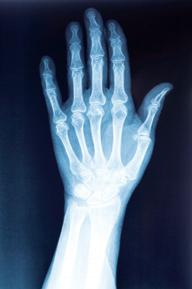

Abb. 7: Benenne die Teile des Skeletts, welche du auf den Röntgenbildern siehst! Schreibe sie auf die Zeilen darunter!

Gib an, welche Verletzungen man mit Hilfe von Röntgenbildern erkennen kann!

Begründe das Aussehen einiger Knochen mit ihrer Funktionsweise!

Röntgenstrahlen können durch unseren Körper dringen und machen unsere Knochen sichtbar. Röntgenbilder werden gemacht, um Verletzungen oder bestimmte Knochenkrankheiten feststellen zu können.